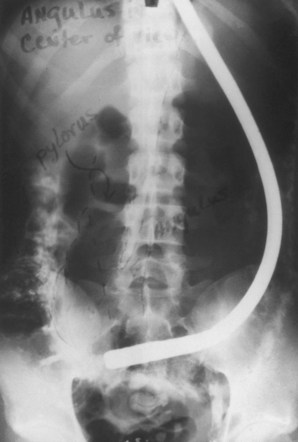

我们和其他人都注意到纤维镜存在一些问题。远端光源会变得过热,除非持续移动镜尖,否则可能会对胃黏膜造成热损伤。在长时间的手术中,胃分泌物中的蛋白质会凝结在球泡和邻近的观察口上,完全遮挡镜头。随着使用单个器械进行手术次数的增加,一些玻璃纤维会断裂,在视野中产生小黑点。这是纤维镜在其整个使用过程中一直存在的问题,尤其是在多个受训人员使用一台纤维镜对多名患者进行手术的培训项目中。侧视镜头妨碍了食道的观察,因此必须盲目地将纤维镜穿过咽口。之前使用的半柔性纤维镜也存在这个问题,但在当时并不被认为是缺陷。柔性本身导致了推进的一些困难,因为试图将器械推过幽门进入肠道会导致胃囊弯曲加剧(图1.10)。虽然有时可以看到十二指肠,但这是通过过度充气胃部并通过幽门观察而实现的,而实际上并没有进入幽门。如果操作者设法将尖端插入十二指肠(这种情况偶尔会发生),视野会位于仪器焦距内,只能观察到“红晕”。其他人也有类似的抱怨

图 1.10有时通过过度充气胃可以获得十二指肠的可视化。